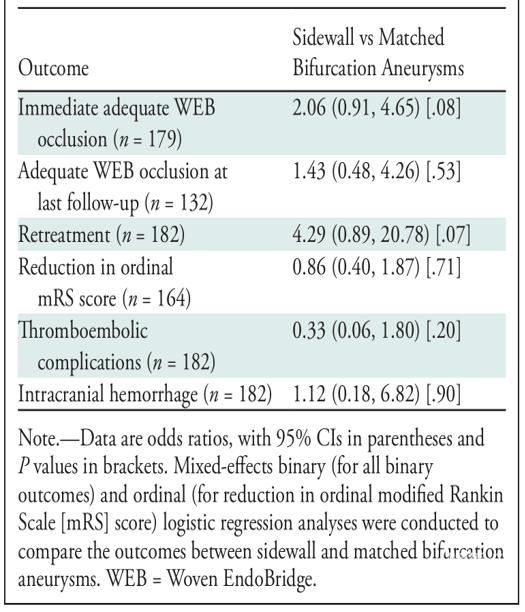

回顾性分析从2011年1月至2021年6月在北美、南美和欧洲22个中心使用WEB治疗颅内动脉瘤的病例资料。比较分叉动脉瘤和侧壁动脉瘤的特征和预后。

91对分叉动脉瘤和侧壁动脉瘤。

两组在最后一次随访时动脉瘤闭塞状态、WEB放置成功率或并发症发生率方面均无显著差异。

最后一次随访的充分闭塞率(adequate occlusion rate)为89%(95% CI,81%-94%;I2,=0%,P=.66)。动脉瘤宽度(aneurysm width)(OR=0.5;P=.03)是完全闭塞的唯一显著预测因子。